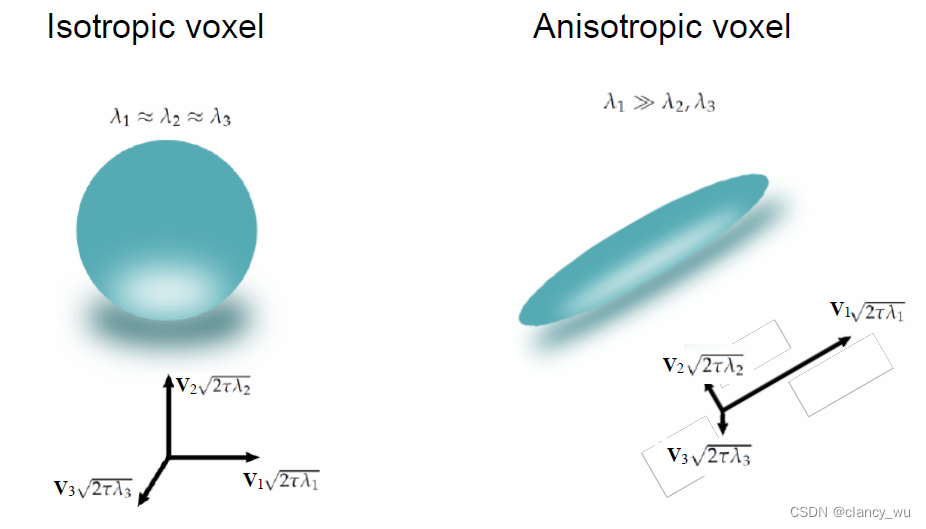

在纤维束中,分子的扩散是各向异性的(anisotropic),水和液体和灰质是各向同性的(isotropic)。这很好理解,简单说就是纤维束中的分子运动只能朝着纤维束的方向扩散(轴突),脑脊液中的分子运动可以朝着周围随意运动,向各个方向运动的概率是相同的,这就是各项异性和各项同性的简单理解。这个是DTI分析的基本知识和背景。

这样,通过这些定义的坐标系,我们就能用公式来表达各向异性和各向同性:

由此,可以得出各向异性的表达公式。各向异性的全称其实是Fractional Anisotropy,FA值,在[0, 1]之间。MD是平均扩散率